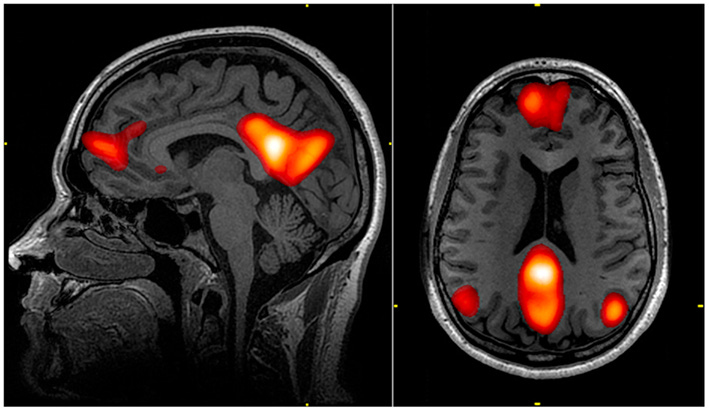

À ce moment, notre cerveau active une zone qu’on appelle le Réseau du Mode par Défaut.

Pour faire simple, cette zone permet de connecter émotionnellement avec l’auteur.

Mais si le lecteur soupçonne que le texte a été généré par une IA (ce qui arrive de plus en plus souvent), notre cerveau arrête de chercher une “âme” ou une intention derrière les mots, car il sait qu’il n’y en a pas.